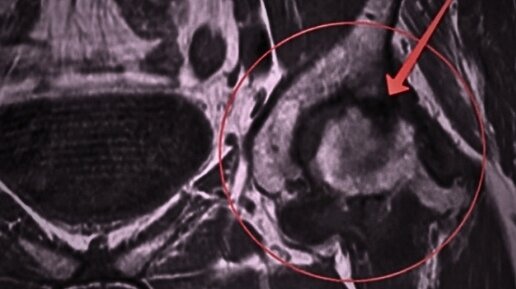

🤔 для тех у кого есть диагноз асептический некроз 🦵 Довольно часто ко мне обращаются с данным диагнозом, и не менее часто задают вопрос о том: "Можно ли избежать операции по замене сустава при асептическом некрозе?" 🗂И на этот вопрос я обязательно отвечу, но обо всем по порядку 🖊Некроз - отмирание ткани;  Асептический подразумевает отсутствие инфекции в поврежденном месте 👉 Основная причина асептического некроза - это острое кислородное голодание тканей, то есть не хватает кровоснабжения;...

Прежде, чем приступить к статье, хотелось бы посоветовать тем из вас, у кого есть проблемы с тазобедренным суставом, ознакомиться с книгой Бубновского Сергея Михайловича: «Вся правда о тазобедренном суставе». Эта книга написана на основании личного опыта Сергея Михайловича, у которого был коксартроз с асептическим некрозом. Также отмечу, что есть такое заболевание как болезнь Пертеса. Очень многое в этой статье можно экстраполировать на это заболевание т.к. в обоих случаях речь про асептический некроз...